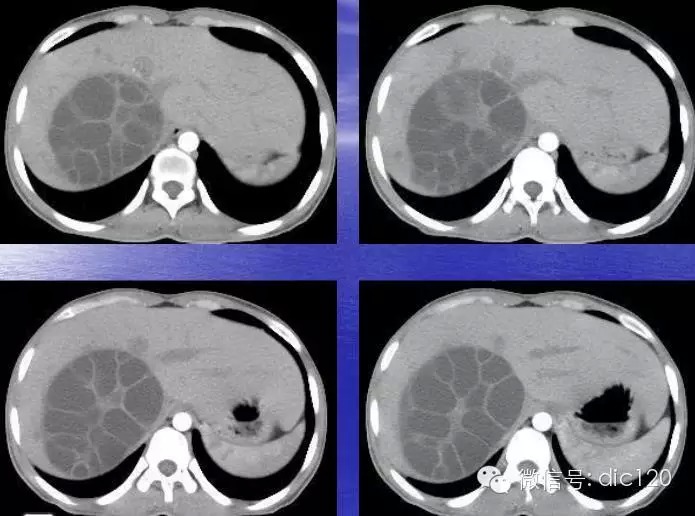

肝包虫病CT表现:

(1)肝内圆形或类圆形低密度区,CT值可在-14~25HU,密度均匀一致,增强后无强化表现。边界清楚,光整。囊壁及囊内分隔有增强效应。

(2)大的囊腔内可见分房结构或子囊(囊内囊)。子囊的数目和大小不一。如子囊主要分布在母囊的周边部分呈车轮状。

(3)囊壁可见钙化,呈壳状或环状,厚薄可以规则,为肝包虫病特征性表现。

(4)因感染或损伤,可造成内囊分离,如内、外囊部分分离表现为双边征;如内囊完全分离、塌陷、卷缩,并悬浮于囊叶中,呈水上荷花征。偶尔完全分离脱落的内囊散开呈飘带状阴影。